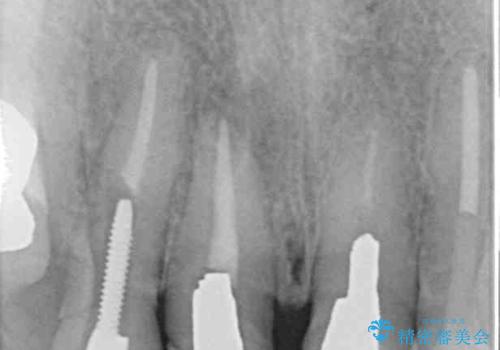

- 前歯が土台ごと外れてしまうとのことで来院された患者様です。

問題の歯は、歯根まで破折している状態で、抜歯が必要と判断されました。

周辺の歯は20年以上前に装着したクラウンで、色合いや形態が気になっているとのことで、オールセラミックブリッジにて補綴治療を行うこととしました。

ところが、土台となる歯は、十分な維持力が得られないほど歯ぐきの中に埋もれており、歯ぐきも腫れやすい状況でした。

まずは土台の歯を引っぱり出し、外科処置により歯肉の状態を十分に整えた上で、オールセラミッククラウンにて補綴することとしました。

元々の土台は歯肉の中に埋もれており、歯肉が著しく腫れている状態だったため、歯を引っぱり出すこととしました。引っぱる期間は2ヶ月ほどで済み、その後歯周外科処置を行ったことで、土台周りの歯肉は腫脹のない健全な状態へと改善されました。